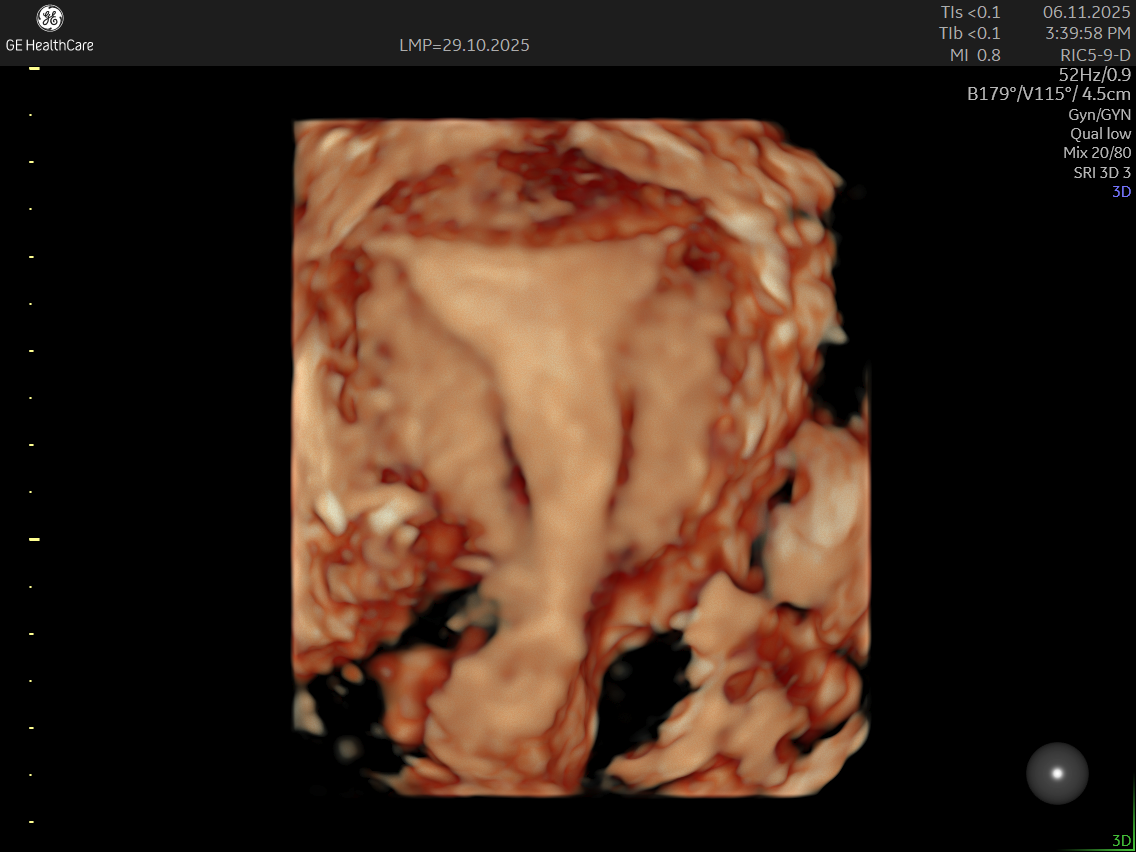

Traditional ultrasounds can miss small or deep infiltrating endometriosis. Advanced gynecological ultrasound, however, combines high-frequency probes, 3D/4D imaging, and specialized Doppler evaluation to provide detailed visualization of the uterus, ovaries, and pelvic structures.

- 3D volumetric scans for a complete anatomical overview

- Color Doppler mapping to study blood flow changes in affected tissues

- Access to 3D/4D ultrasound technology and advanced probe systems